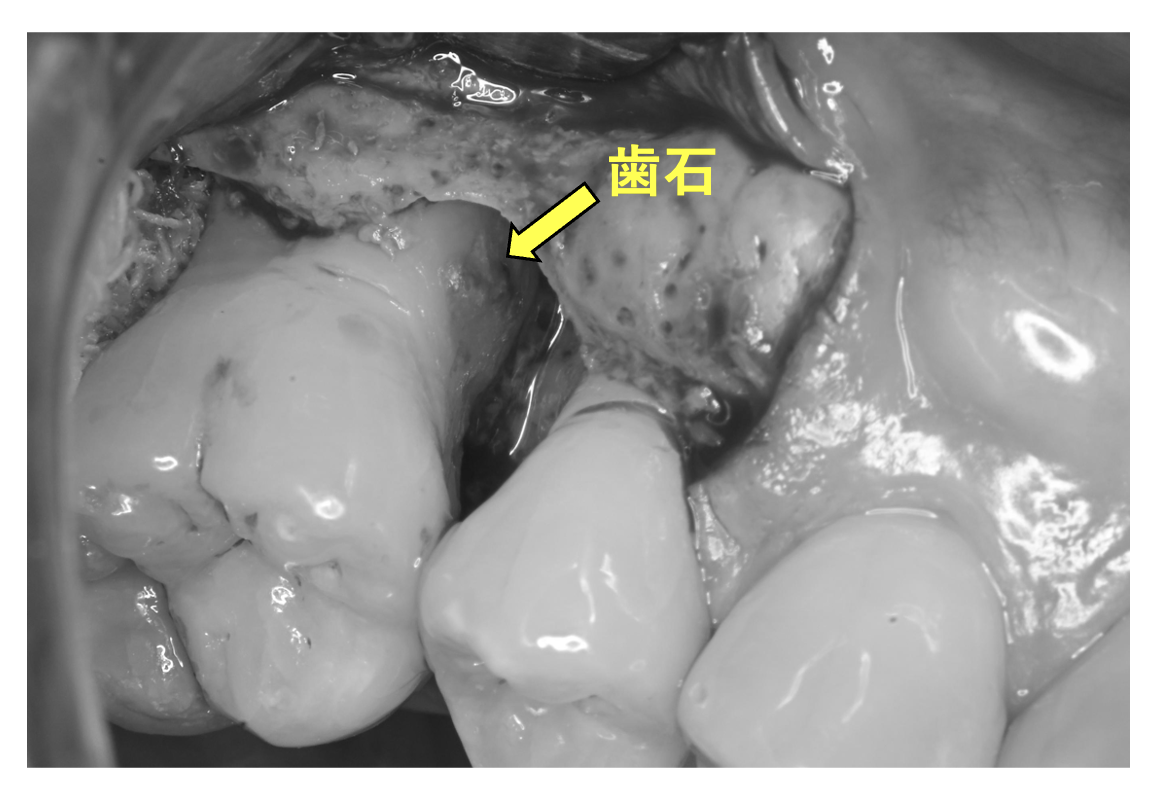

歯周病で歯を支える歯が溶ける?

歯周外科時(歯石の確認)

| 主訴 | 歯科医院に定期的に通っているが、深い歯周ポケットが残存しているのでかかりつけ医より当院を紹介されて来院。定期的に歯茎が腫れるとのこと。 |

| 治療内容 | 歯周基本治療終了後に歯周組織再生療法を実施 ポケット8mmを超える部位では大きな骨欠損を認める。この原因は『歯石』、つまりは細菌の塊がその場所にいたことで歯を支える骨が溶けてしまったのです。 |

| 治療期間 | 9ヶ月 歯周基本治療(2ヶ月) 歯周外科治療、歯周組織再生療法(1ヶ月) 歯周組織再生療法後は6ヶ月経過を確認しメインテナンスへ |

| 費用 | 歯周組織再生療法(サイトカイン+骨補填剤の併用療法) 165,000(1部位につき) |

| リスク・副作用 | サイトカインと骨補填剤を併用した歯周組織再生療法では術後の腫れや痛みを生じる場合があります。 歯周組織(特に歯槽骨)の再生が認められた後も定期的なメインテナンスやご自身でもブラッシングが大切です。それを怠ると再発や悪化につながりますのでご注意ください。 *当院ではブラッシング指導を徹底し、ご自身できちんと口腔内環境を管理できるようご協力いただいております。ブラッシング状況が改善されない場合は歯周外科治療へ進まないこともありますのでご理解ください。 |